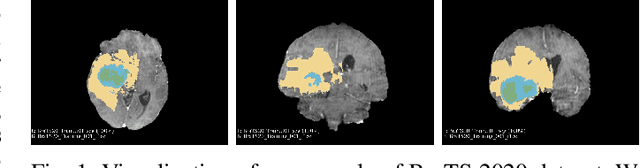

Abstract:Brain tumor segmentation models have aided diagnosis in recent years. However, they face MRI complexity and variability challenges, including irregular shapes and unclear boundaries, leading to noise, misclassification, and incomplete segmentation, thereby limiting accuracy. To address these issues, we adhere to an outstanding Convolutional Neural Networks (CNNs) design paradigm and propose a novel network named A4-Unet. In A4-Unet, Deformable Large Kernel Attention (DLKA) is incorporated in the encoder, allowing for improved capture of multi-scale tumors. Swin Spatial Pyramid Pooling (SSPP) with cross-channel attention is employed in a bottleneck further to study long-distance dependencies within images and channel relationships. To enhance accuracy, a Combined Attention Module (CAM) with Discrete Cosine Transform (DCT) orthogonality for channel weighting and convolutional element-wise multiplication is introduced for spatial weighting in the decoder. Attention gates (AG) are added in the skip connection to highlight the foreground while suppressing irrelevant background information. The proposed network is evaluated on three authoritative MRI brain tumor benchmarks and a proprietary dataset, and it achieves a 94.4% Dice score on the BraTS 2020 dataset, thereby establishing multiple new state-of-the-art benchmarks. The code is available here: https://github.com/WendyWAAAAANG/A4-Unet.